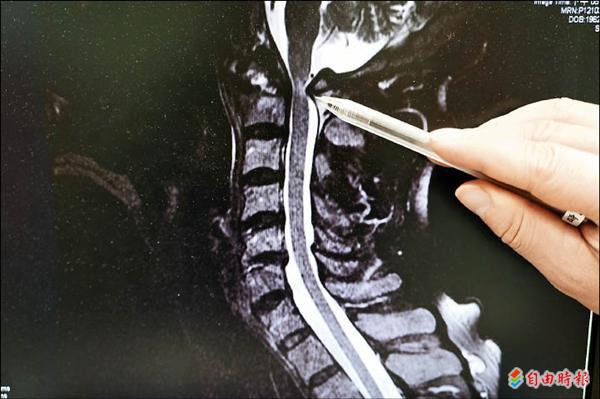

大林慈濟醫院副院長陳金城說,核磁共振檢查影像發現,病患脊髓受到第一頸椎骨壓迫,導致四肢無力癱瘓。由於患者經過一年多的時間,骨折的頸椎骨已無法再復位,必須靠頸骨切除減壓。手術時將第一頸椎壓迫脊髓的骨頭切除,再藉由顱骨、頸骨骨釘固定系統,把滑脫移位的骨頭固定,術後逐漸恢復行走及上肢活動能力。